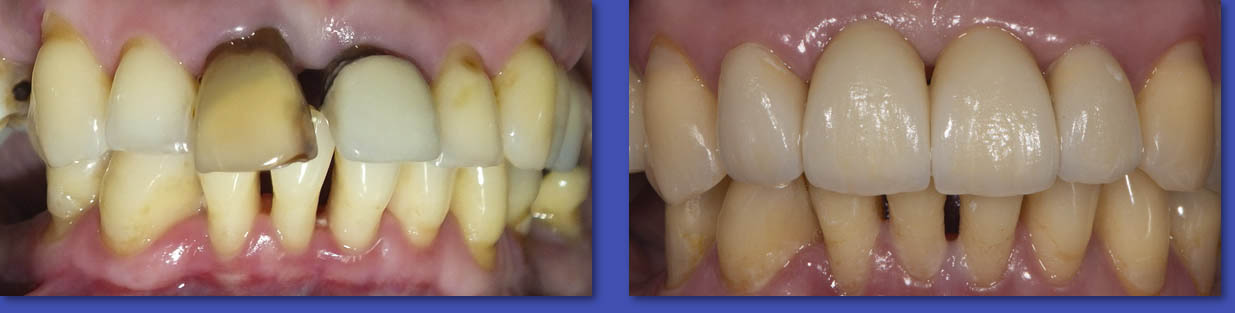

5. PRÓTESIS FIJA (CORONAS Y PUENTES)

La prótesis Fija es el tratamiento indicado en aquellos casos en que la corona del diente está afectada completamente y se debe rehabilitar en forma íntegra, además en el caso de los puentes sirve para reponer de forma fija, dientes que fueron extraídos. La mayoría de las veces un diente con tratamiento de conducto requiere una corona para ser rehabilitado.

ANTES

DESPUÉS